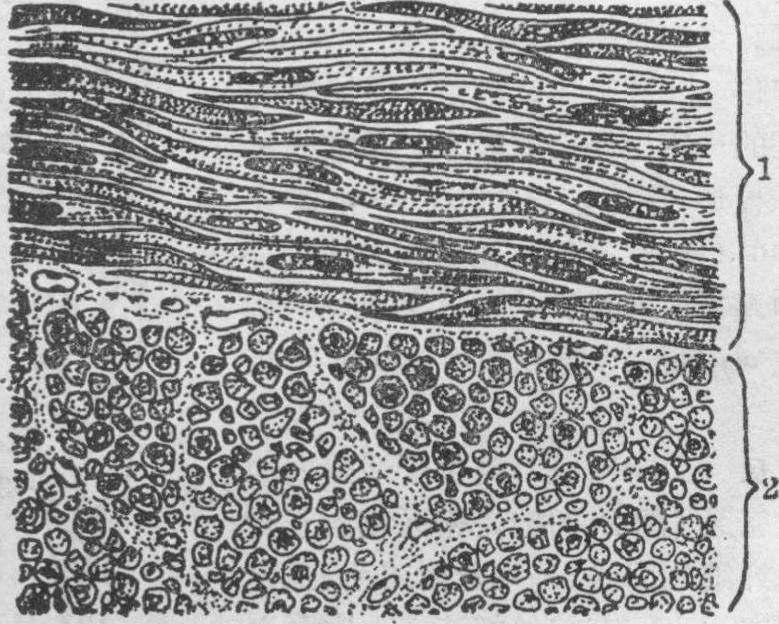

平滑肌组织是由平滑肌纤维构成,肌纤维间有少量结缔组织。平滑肌纤维不显横纹,受自主神经支配,属于不随意肌,常呈节律性收缩,收缩缓慢持久。平滑肌纤维多集合成束或成层,排列规则整齐,主要构成一些器官的管壁,如胃肠道、呼吸道、泌尿生殖管道、血管、淋巴管等的肌层。此外如立毛肌、睫状肌、虹膜肌及阴囊、阴茎、乳头等处的平滑肌均成束分散存在。梭形平滑肌纤维平行排列,一条肌纤维的粗部和另些条肌纤维的细部彼此交错,相互结合成肌束或肌层(图1)。结缔组织内有血管、淋巴管和自主神经分布到肌束或每条肌纤维之间。网状纤维呈环形缠绕。弹性纤维的排列同肌纤维的纵轴一致,弹性纤维与肌纤维相连处常以半桥粒连接,两者共同形成一个功能单位。肌纤维周围也有胶原纤维,它可对平滑肌纤维的过度伸展起限制作用。横切面可见肌纤维直径粗细不等,粗的是肌纤维中部,常见有细胞核;细部为肌纤维两端部,无核(图1)。平滑肌主要功能是产生胃肠蠕动、调节血流、促使腺体分泌及使阴囊和乳头等部位皮肤皱缩等。平滑肌纤维和成纤维细胞是性质相近的细胞,肌纤维间虽有三种结缔组织纤维却很少见成纤维细胞,近年已知肌纤维可产生结缔组织的细胞间质——纤维和基质。

图1 平滑肌

1.平滑肌纵切面 2.平滑肌横切面

平滑肌纤维的微细结构 平滑肌纤维呈梭形,其中部较宽,直径约为3~6μm,越近两端越细(图1)。其长度因所在器官和机能状态不同而有很大差异,小血管壁的平滑肌纤维只有20μm,而妊娠子宫壁的平滑肌纤维长可达500μm,一般为100~200μm左右。细胞核位于肌纤维中央部,常呈长圆形或杆状,与肌纤维长轴平行,核内染色质呈稀疏状,有1~2个核仁。有时核出现螺旋状扭曲,这是肌纤维收缩所致。电镜下,平滑肌纤维表面包有肌膜,厚约8~15nm。肌膜外有一层细胞衣和基膜。肌膜内陷形成一些圆形小泡,称质膜小泡或吞饮小泡(图2)。质膜小泡大小约50~60nm×70~80nm,小泡开口处略窄,约为30~40nm,多成群位于密区之间。其功能可能与酶的活性或细胞内、外离子转换有关。有人证明,质膜小泡与肌浆网系统贴连,认为它相当于骨胳肌纤维的横小管系统。肌浆中含有肌丝,肌浆网、线粒体、高尔基复合体、中心粒、糖原颗粒等,还有平滑肌纤维所特有的密区和密体。